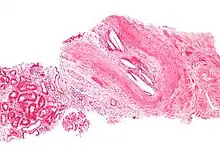

Micrograph showing a cholesterol embolus in a medium sized artery of the kidney. Kidney biopsy. H&E stain.

The microscopic examination of tissue (histology) gives the definitive diagnosis. The diagnostic histopathologic finding is intravascular cholesterol crystals, which are seen as cholesterol clefts in routinely processed tissue (embedded in paraffin wax).[7] The cholesterol crystals may be associated with macrophages, including giant cells, and eosinophils.

The sensitivity of small core biopsies is modest, due to sampling error, as the process is often patchy. Affected organs show the characteristic histologic changes in 50-75% of the clinically diagnosed cases.[3][5] Non-specific tissue findings suggestive of a cholesterol embolization include ischemic changes, necrosis and unstable-appearing complex atherosclerotic plaques (that are cholesterol-laden and have a thin fibrous cap). While biopsy findings may not be diagnostic, they have significant value, as they help exclude alternate diagnoses, e.g. vasculitis, that often cannot be made confidently based on clinical criteria.